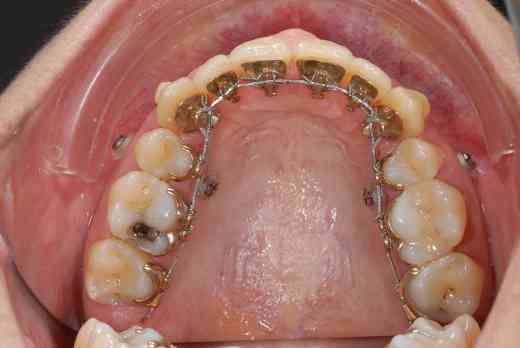

3 mois de mini vis et d'élastocs de classe II :-))

chuis pas belle comme ça? :-)))

La question qu’on peut se poser est : pourquoi les vis ont-elles été placées un endroit où elles ne pouvaient que gêner le recul latéral supérieur qui avait justifié leur pose.

C’est dans doute pour cela qu’elles ont été enlevées au bout de trois mois seulement..

la technique linguale est plus difficile à maîtriser, les points d'appui plus difficiles à trouver (cf minivis qui doivent rester esthétiques, c le but du traitement)